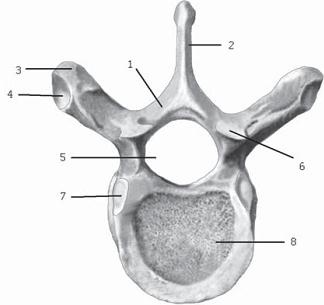

Рисунок № 11. Грудной позвонок. Вид сверху

1 — дуга позвонка; 2 — остистый отросток; 3 — поперечный отросток; 4 — рёберная ямка поперечного отростка; 5 — позвоночное отверстие; 6 — верхний суставной отросток; 7 — верхняя рёберная ямка; 8 — тело позвонка